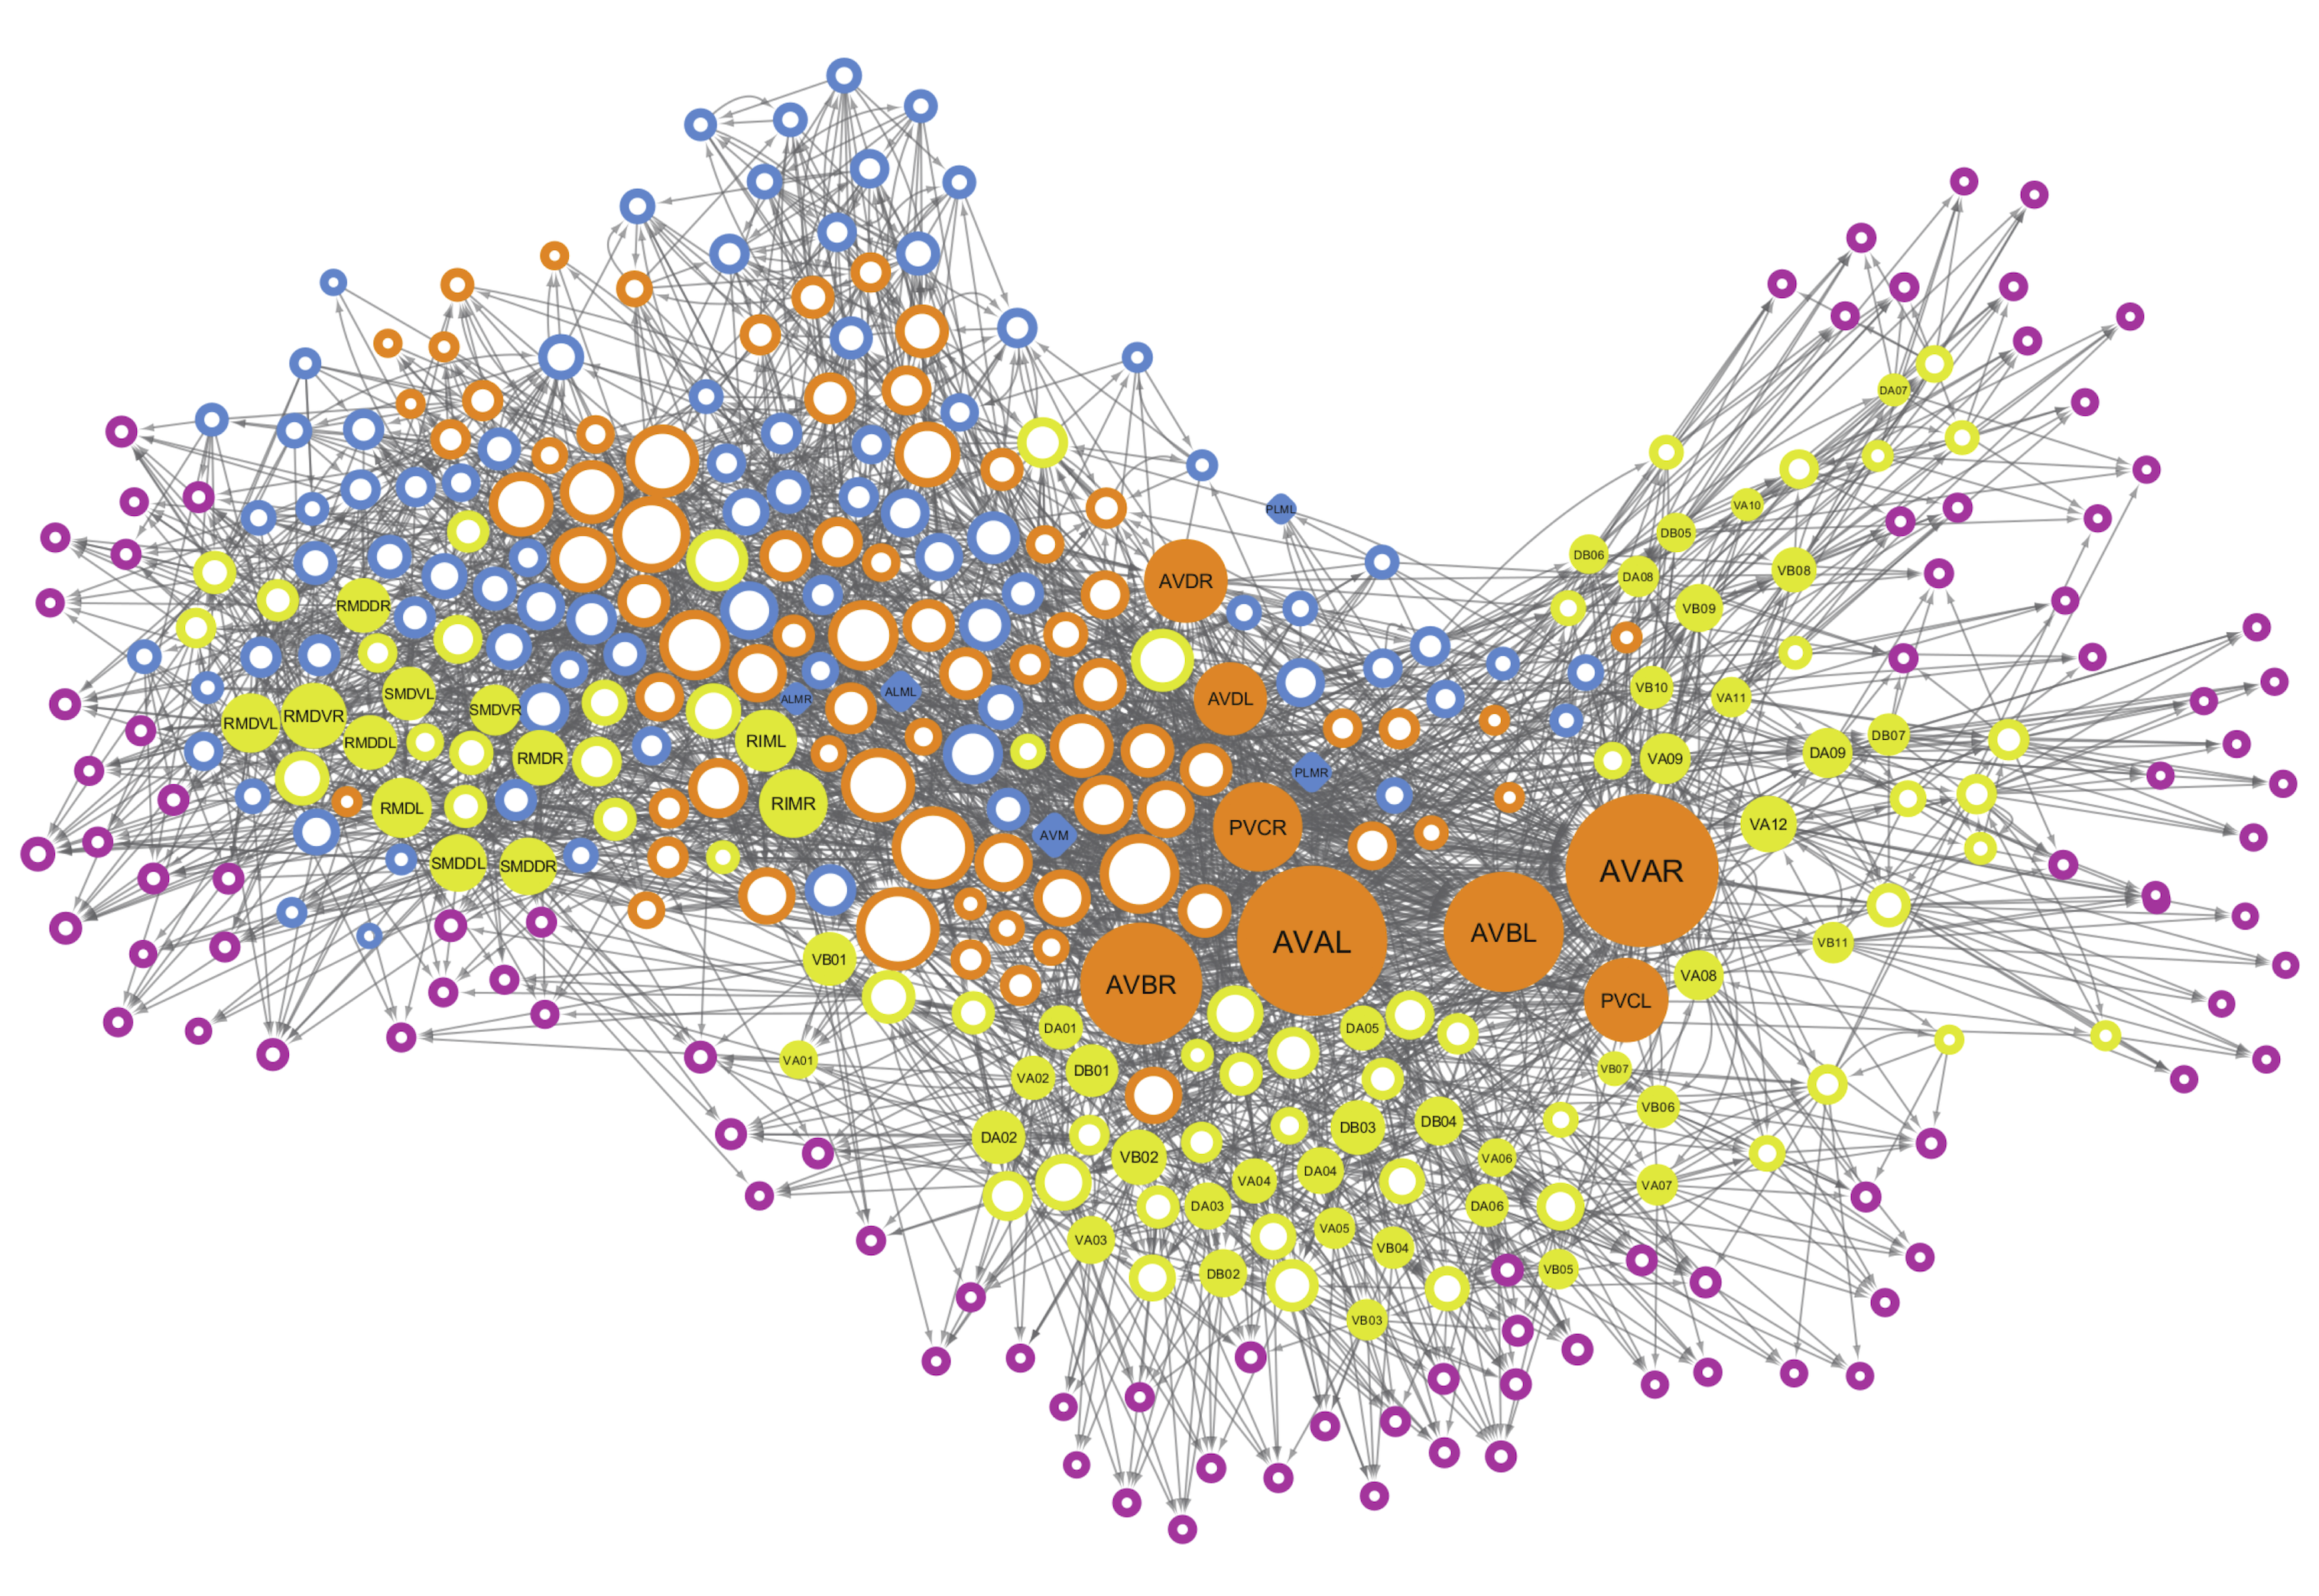

Коннектом мозга: визуализация связей и нейронных путей